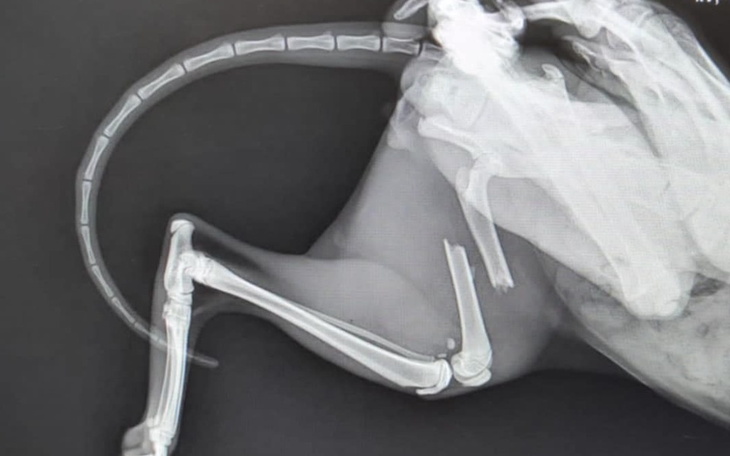

Kot-bezdomniak przybłąkał się pod drzwi moich przyjaciół.Został,dali mu dom i schronienie. Niestety wczoraj wymknął się z domu. Po całej nocy poszukiwań byliśmy już zrezygnowani. Rano kot sam wrócił do domu obolały. Po prześwietleniu stwierdzono złamanie kości udowej,przypuszczamy ,że kot został potrącony przez samochód. Koszt operacji to 2000 zł. Bardzo proszę o pomoc w zebraniu tej kwoty. Moi przyjaciele zostali poinformowani o zbiórce. Jeśli czujecie w sercu potrzebę wsparcia mojej prośby,proszę o pomoc.